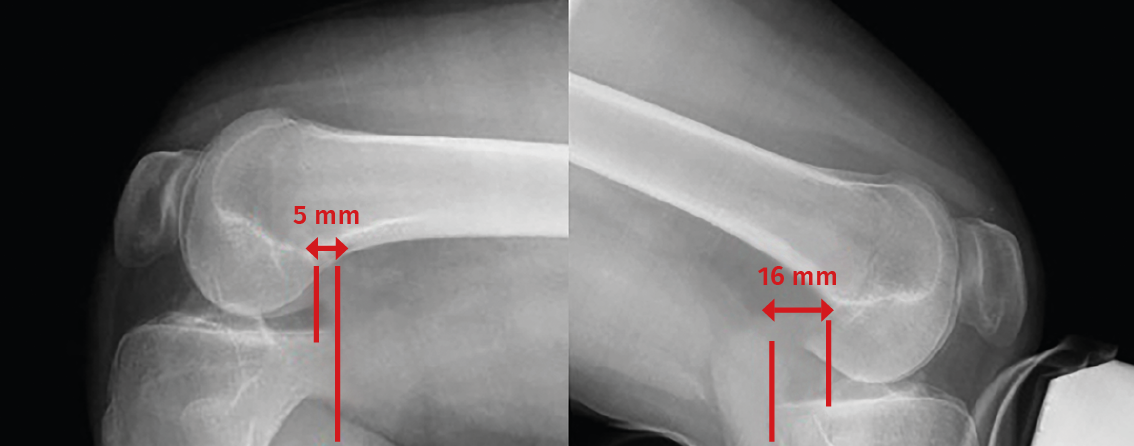

Although the diagnosis of PCL rupture is essentially clinical, and instability is quantified from stress radiographs, magnetic resonance imaging (MRI) is the technique of choice for the diagnosis and follow-up of PCL lesions subjected to conservative management, and affords excellent information on the presence of associated injuries - not only ligament damage but also meniscal or chondral lesions. In addition, MRI is able to distinguish between acute and chronic injuries, since the absence of soft tissue edema and of bone contusion (usually affecting the anterior portion of the tibia) is indicative of a chronic lesion(13,14).

Posterior cruciate ligament injuries are divided into three types according to their MRI characteristics: partial or intrasubstance lesions (Figure 6A), complete lesions (Figure 6B) and avulsion fractures at the tibial insertion (Figure 6C)(13,14). Most complete lesions occur in the middle portion of the ligament, which is not correctly visualized in the axial and coronal planes; the gold standard therefore is evaluation of images in the sagittal plane(13,14).

Figure 6. A: magnetic resonance imaging (MRI) sagittal view in T2-weighted sequencing, showing partial rupture; B: complete rupture of the posterior cruciate ligament (PCL); C: MRI sagittal view in T1-weighted sequencing of the left knee. The white arrow indicates avulsion of the PCL with a bone fragment in the tibial insertion.